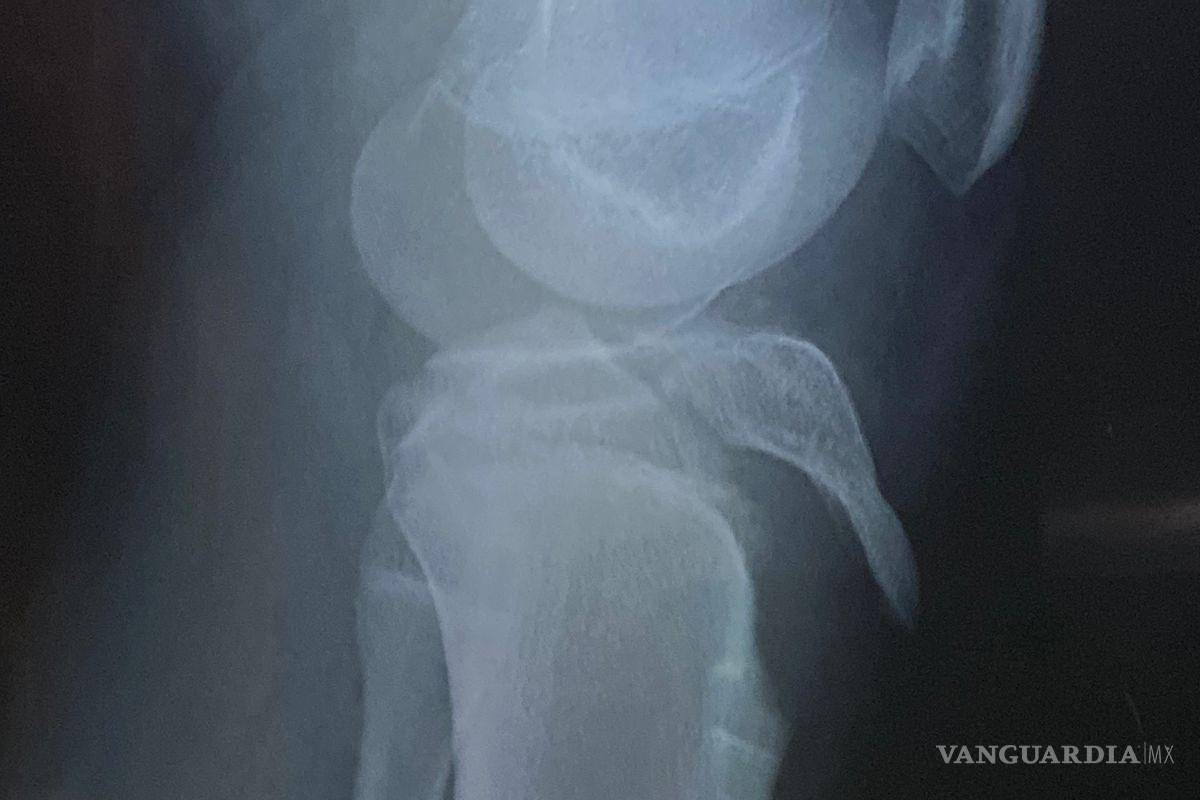

El menor participaba en prácticas para una actividad llamada “olimpiada” cuando resultó con una grave lesión en la rodilla que requirió cirugía para la colocación de tornillos.

$!La cirugía del estudiante implicó la colocación de tornillos en la tibia, costos que inicialmente cubrieron los tutores.